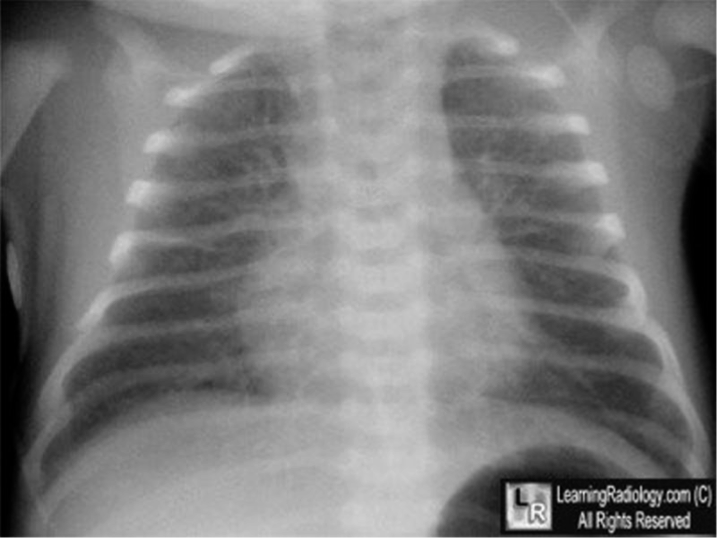

Radiographic Findings

• Prominent perihilar streaking reflecting fluid in the interstitium

• Patchy infiltrates

• Fluids in the horizontal fissure on fifth right costal

• Hyperinflated lung